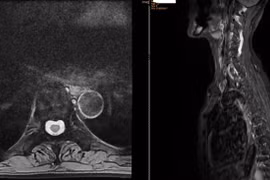

Bệnh nhân 64 tuổi tại Hà Nội điều trị loãng xương nặng, nguy cơ gãy xương cao, nhấn mạnh tầm quan trọng của chẩn đoán sớm và điều trị hiệu quả.